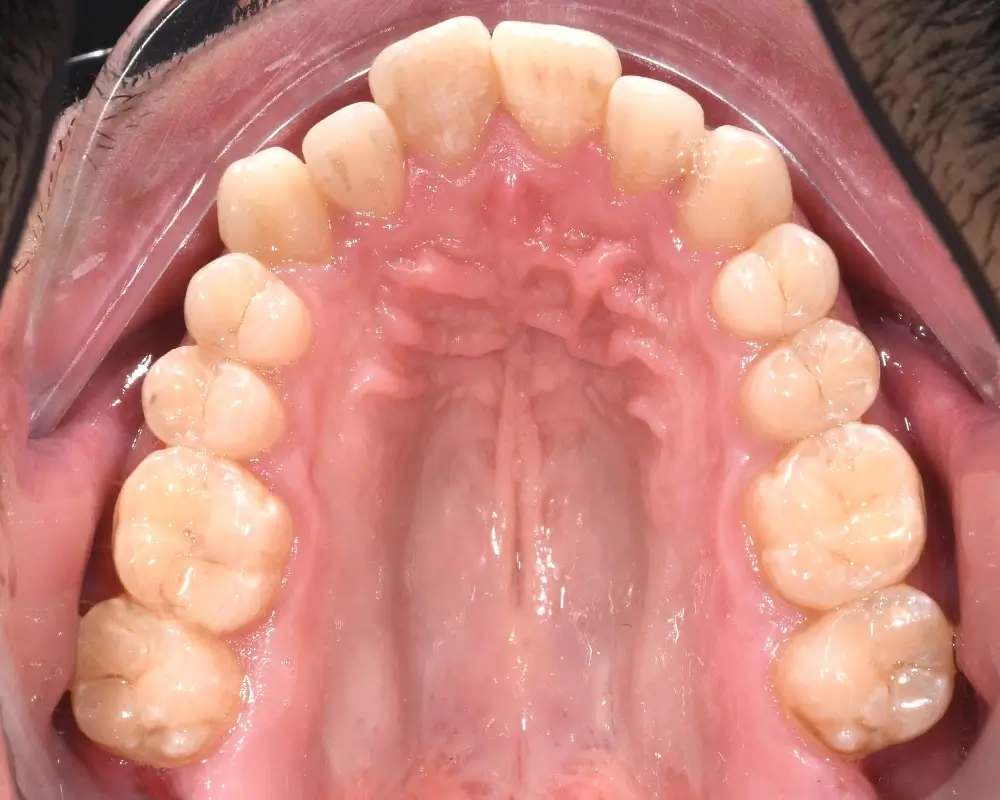

Открытый прикус - Кейс 3

Эффективность устранения дефекта прикуса посредством элайнеров FlexiLigner.

Результаты лечения